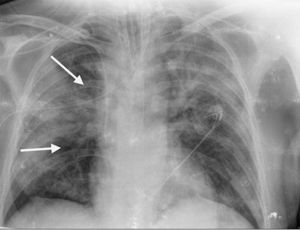

Paciente de 64 años, como único antecedente personal hipertenso, ingresa en la UCI con diagnóstico de SDRA grave secundario a neumonía bilateral por COVID-19. En radiografía de tórax se observa un patrón alveolointersticial bilateral que afecta más al pulmón derecho, sobre todo al campo medio (fig. 1, indicadores flechas). En la analítica destaca un dímero D muy elevado (28.970ng/ml) y ante la sospecha de TEP se realiza ecocardiografía transtorácica apreciándose sobrecarga de presión de VD con signo de McConnell positivo. Dado los hallazgos ecocardiógrafos, se inició tratamiento anticoagulante con heparina de bajo peso molecular (enoxaparina 1mg/kg/cada 12h) y se solicitó angio-TAC torácica para confirmación diagnóstica, evidenciándose defecto de repleción en arteria del segmento lateral del lóbulo medio (flechas en figuras 2 y 3) en relación con TEP. Además existe una afectación difusa bilateral y extensas áreas de patrón en empedrado en relación con el proceso infeccioso vírico (figs. 2 y 3). Se mantuvo el tratamiento anticoagulante hasta el alta sin complicaciones hemorrágicas asociadas.